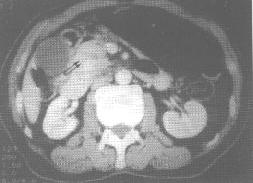

胰头、钩突癌。CT增强钩突平面示胰头、钩突内低密度肿块(下图双箭头),致胆总管(中图三角箭头)及主胰管梗阻、扩张(上图白箭头)形成“双管征”。 | |

1.X线表现: 上消化道钡餐造影可显示十二指肠肠曲扩大,内侧壁僵直不规则,可呈倒“3”字征。 2.超声表现: 胰腺变形,可显示限局性、分叶状肿块,肿瘤内多呈低回声,内含不均匀光点,如有肿块内坏死则探及不规则液化暗区。常合并胆总管或(和)胰管扩张。 3.CT表现: (1)胰腺肿块,密度均匀或不均匀,边缘可呈分叶状,较大肿块内可见低密度坏死区。 (2)胰头部肿瘤可显示胰体、胰尾萎缩,肠系膜上动、静脉移位。若肿块发生在钩突部则尖端变圆钝,示规则或隆起的肿块。 (3)增强扫描肿瘤多呈低增强,密度低于邻近胰腺密度,因此有助于发现较小的肿瘤。 (4)胰头肿瘤多合并肝内、外胆管扩张,胰管扩张及胆囊增大,在适当的层面,扩张的总胆管、胰管同时显示,称“双管征”。 (5)肿瘤可侵犯胰腺周围器官和组织,胰头癌常累及压迫总胆管,引起梗阻性黄疸,也可侵及十二指肠,致十二指肠肠曲扩大或梗阻,侵及肠系膜上动、静脉。如胰体尾部肿瘤常累及脾门、左肾、降结肠、胃后壁等。 4.MR表现: T1加权像肿块呈不规则低信号,T2加权像肿瘤信号为明显高信号。 |